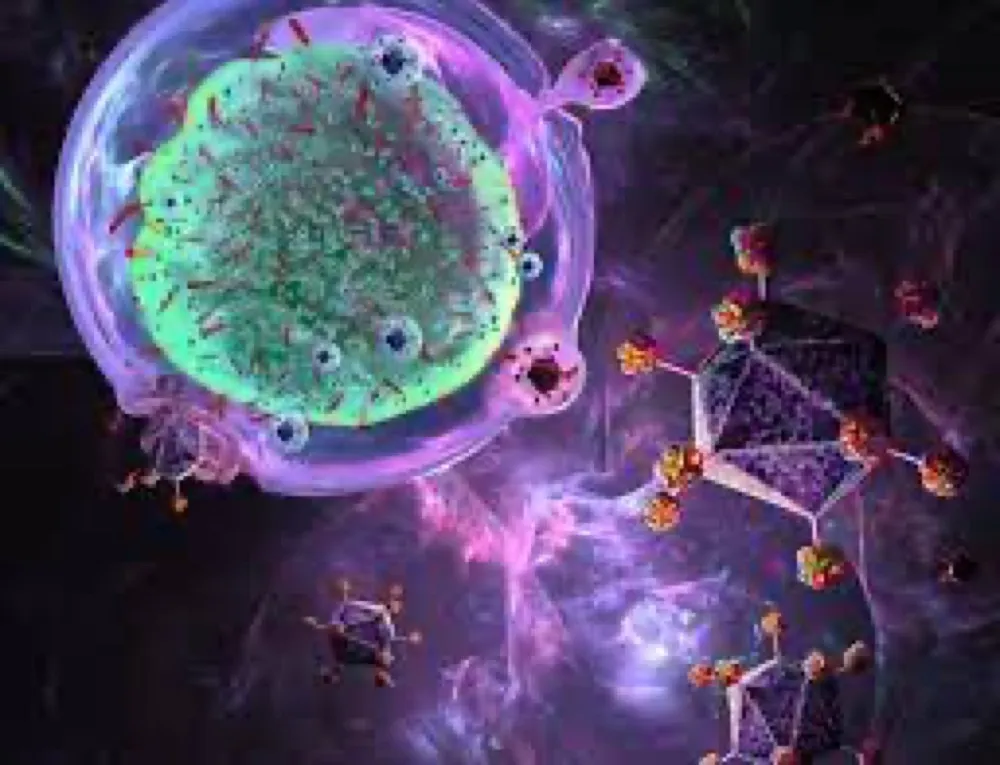

Este vídeo apresenta, de forma didática e baseada em evidências, os principais achados da tese de doutorado sobre amiloidose renal, com foco em proteômica glomerular e ativação do complemento. São discutidos aspectos diagnósticos, implicações fisiopatológicas e correlações clínico-patológicas relevantes para a prática do nefrologista. O conteúdo sintetiza dados inéditos de matriz extracelular glomerular e diferencia perfis entre subtipos de amiloidose. Trata-se de um material aprofundado e acessível, ideal para atualização de especialistas na área.